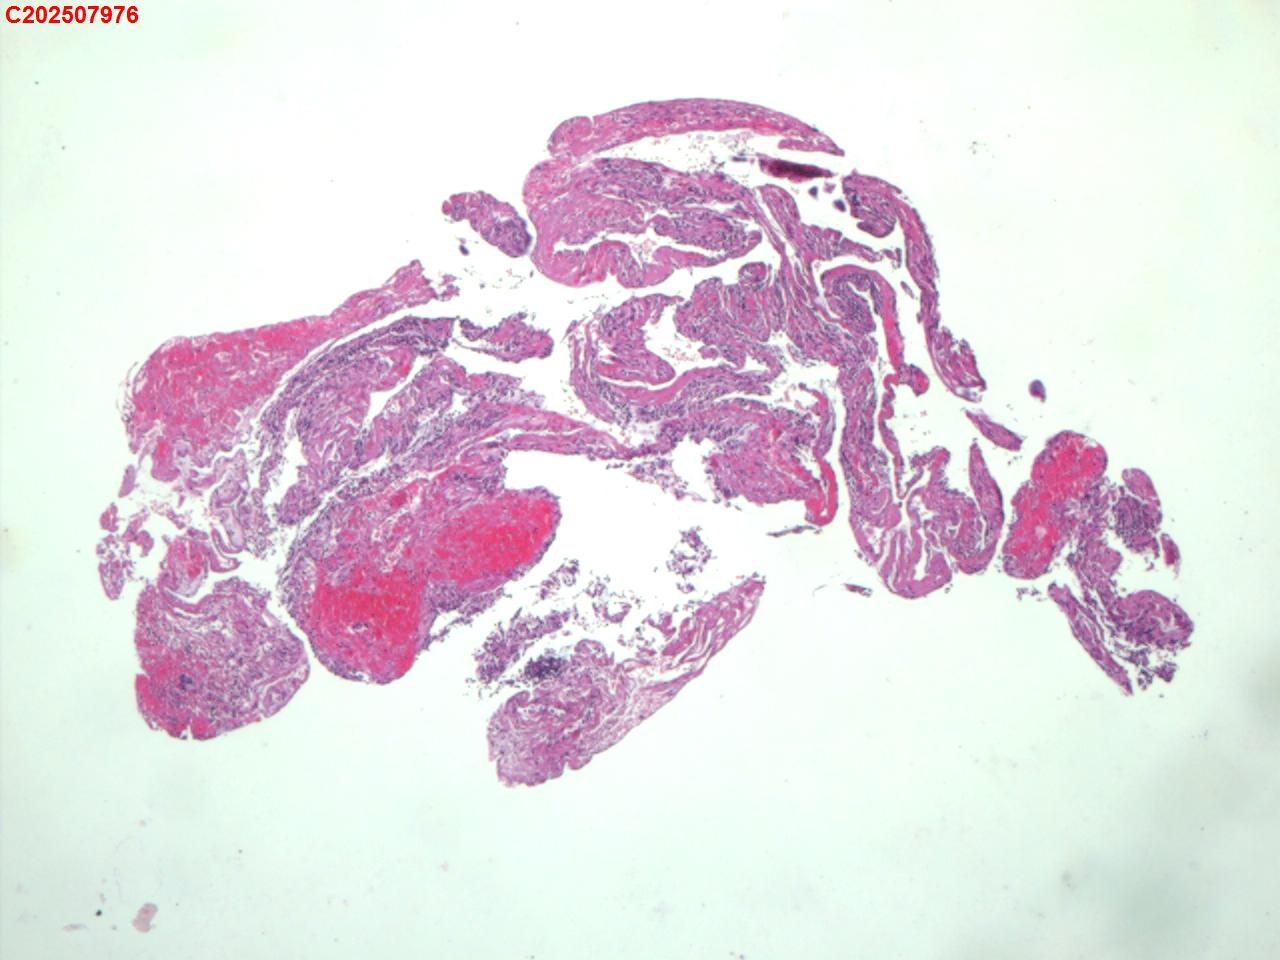

右肺上叶开口处 气管镜咬检

性别

男

年龄

65岁

临床诊断

一般病史

肺TB

标本名称

大体所见

右肺上叶开口上缘处可见肉芽增生,予咬检。

感觉:炎性纤维组织增生